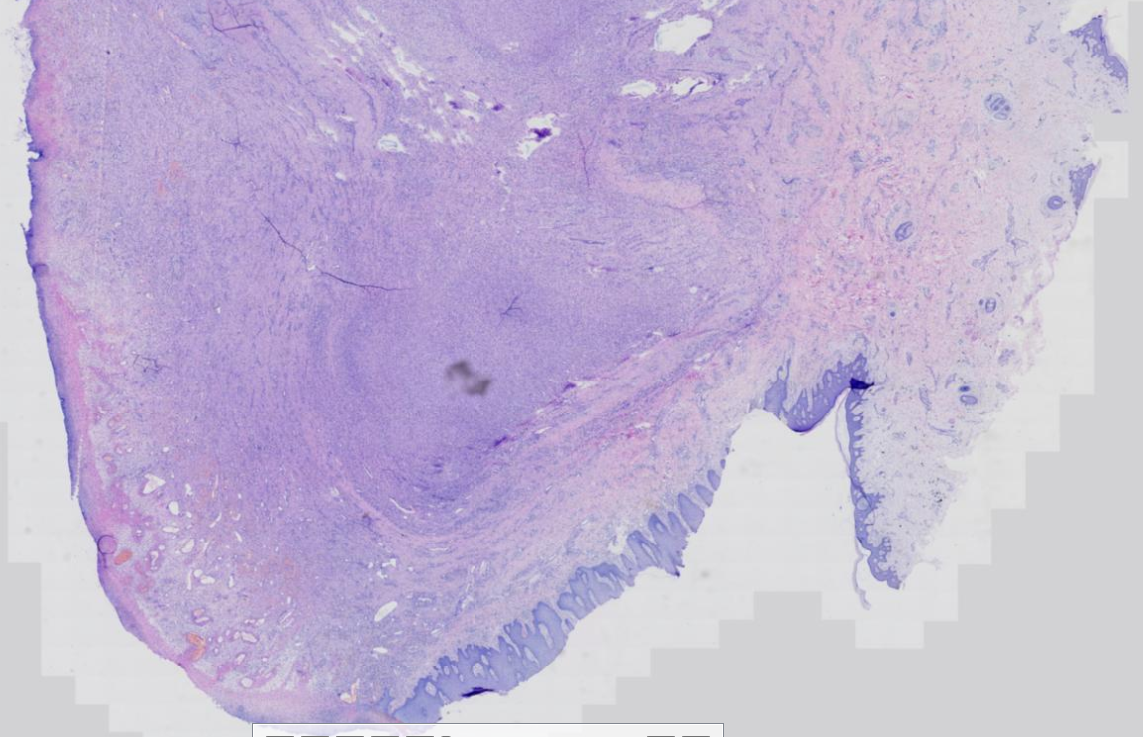

背部肿物,皮赘?

性别

女

年龄

73岁

临床诊断

肿物

一般病史

背部肿物24年

标本名称

背部皮肤肿物

大体所见

带皮肤肿物,体积3*2.5*2cm,表面部分瘤体被皮肤包裹,切面灰白质中。

软纤维瘤。